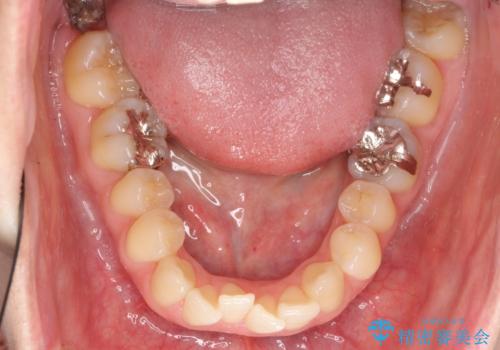

- 前歯2本が後ろに引っ込んでいる状態でした。

マウスピースで歯を抜かずに矯正しました。

左上4番は、虫歯治療をして、セラミッククラウンで修復しています。

一般的にマウスピースを装着した状態で歯ぎしりをしてしまうと、奥歯のかみ合わせが弱くなりやすいため、リテーナーはマウスピースではなく、上下の歯が当たるようなホーレータイプが適しています。